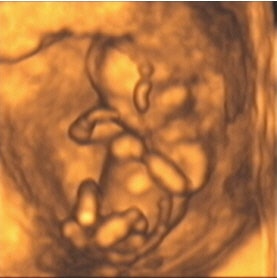

![]() |

| Figure 7, a 3-D ultrasound image of the fetus at 13 weeks gestation. Image courtesy of Stefano Ciatti, M.D. |